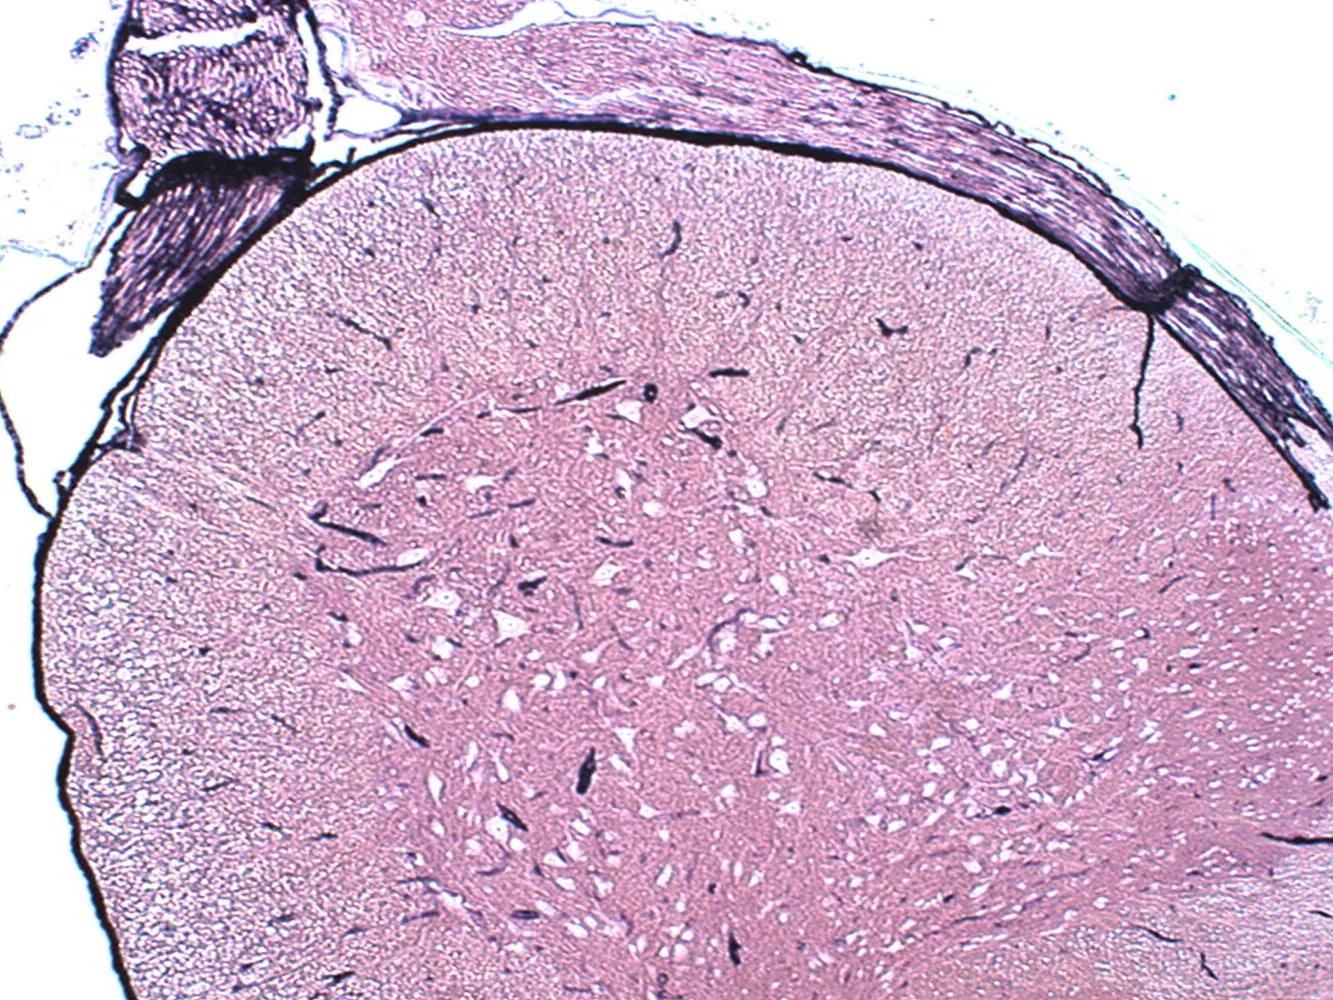

科學新發現丨打破百年認知? 腦脊液不只存在于大腦和脊髓中